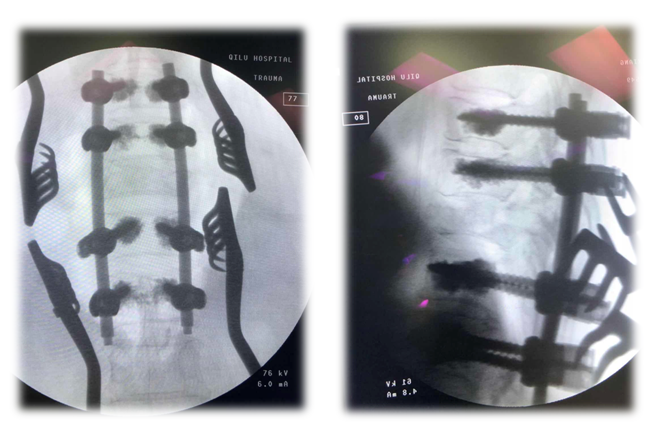

术后影像学

术中透视

术后X线